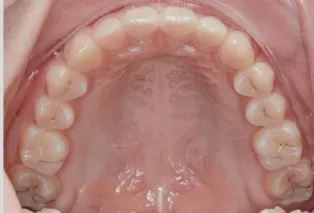

Photos intra-orales après traitement